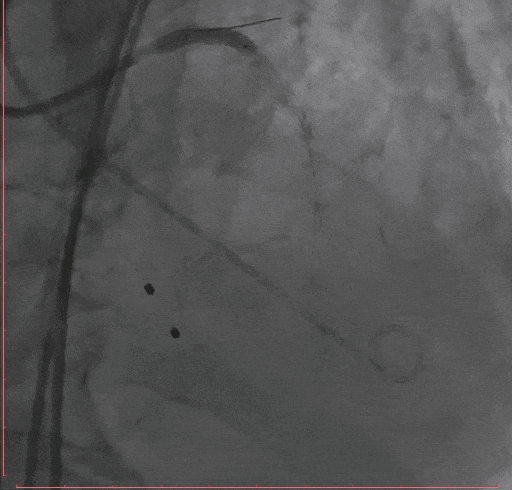

Step 2.冠脉造影

Step 3.导丝跨主动脉瓣后,干预冠脉病变,球囊无法通过LAD病变,予以旋磨

Step 4 旋磨后予以前降支支架植入